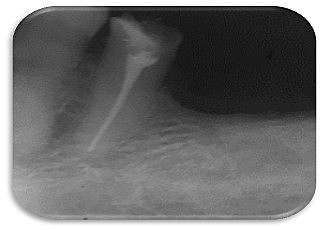

• Serie radiográfica

Serie radiográfica

Se realiza la toma de radiografías peri apical. Se observa pérdida ósea considerable así como ensanchamiento periodontal en OD 1.1 y 2.1.